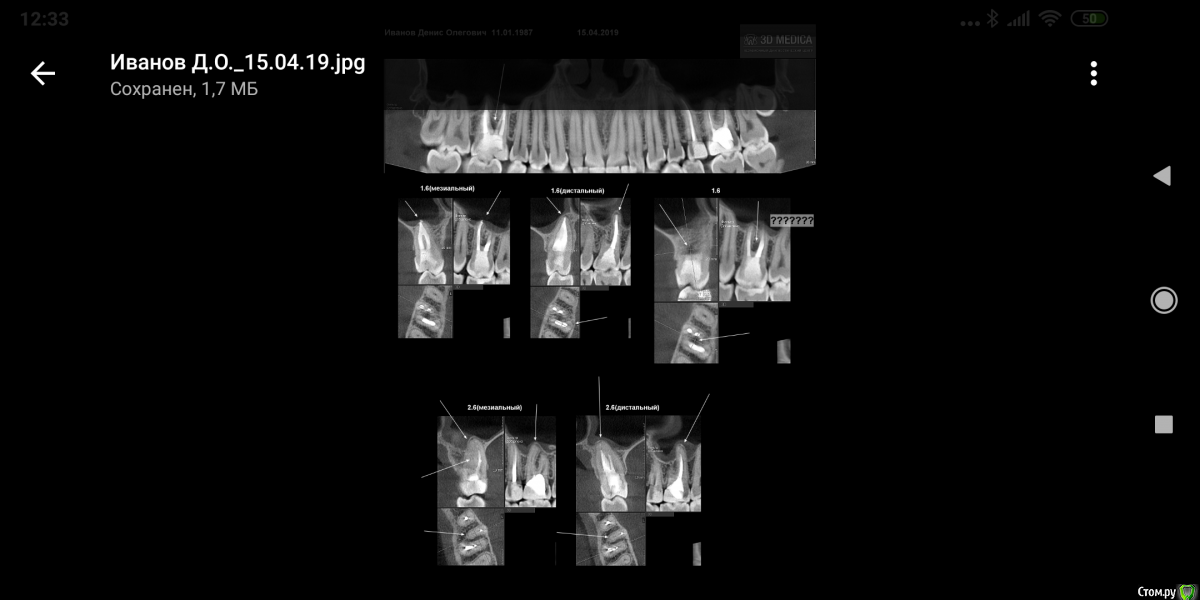

Dench Опубликовано 6 февраля, 2017 Поделиться Опубликовано 6 февраля, 2017 (изменено) Добрый день, уважаемые! Просьба помочь определиться с дальнейшей тактикой: лечить или удалять 26 зуб. На руках имеется панорамный снимок и КТ с расшифровкой. После панорамы у терапевта возникло подозрение на кисту у корня 26 зуба. Панораму делал совершенно случайно в детской стоматологической клинике. Для подтверждения диагноза сделал КТ размером 12 на 8,5, заключения следующие:2.6 зуб — депульпирован. Коронковая часть — восстановлена пломбой с нарушениемкраевого прилегания — удалено администраторомна мезиальной контактной поверхности на 2/3 толщиныдентина. Вариант строения — три корня, ДЩ и небный корни срослись между собой / четыре канала, МЩ корень имеет два канала, открывающихся одним апикальным отверстием. МБ1 канал, канал ДЩ корня и канал небного корня негомогенно, неплотно обтурированы пломбировочным материалом на 2/3 длины каналов, на остальном протяжении каналы облитерированы. МБ2 канал свободен от пломбировочного материала. Определяется расширение периапикального периодонтального пространства МЩ корня шириной до 0,8 мм, небного корня шириной до 0,9 мм.Пародонт: патологической убыли костной ткани не выявлено.На томограммах и реконструктивных снимках околоносовых пазух и полости носаустановлено следующее:В/ч синусы гиперпневматического типа. Контуры видимых стенок четкие, не прерываются. Определяется утолщение слизистой оболочки в/ч синусов: справа до 2,4 мм, слева до 2,8 мм. В толще слизистой оболочки нижней стенки левого в/ч синуса определяется зона повышенной плотности с четкими, ровными контурами, овальной формы, не связанная с костными стенками левого в/ч синуса, не нарушающая целостность кортикальной пластинки, размерами 3,1х1,8х2,7 мм (ШхВхГ).ДИАГНОСТИЧЕСКОЕ ЗАКЛЮЧЕНИЕ:Частичная вторичная адентия.Ретенция зуба 2.8.удалено администраторомзубов 1.5, 2.5, 3.5, 3.6 (?).Вторичный удалено администратором зубов 1.6, 2.6.Хронический удалено администратором зуба 2.6.Двустороннее утолщение слизистой оболочки в/ч синусов.Зона повышенной плотности в толще слизистой оболочки левого в/ч синуса (кальцинат).Терапевт настаивает на удалении. Был у хирурга. Его мнение - зуб не удалять, а лечить. Если все же решусь удалять зуб, то возникают следующие сомнения (основаны на моих догадках):- так как пазухи гиперпневматического типа, то существует вероятность перфорации пазухи с дальнейшими осложнениями и необходимостью пластики сообщения полости рта с вч пазухой?- так как зуб кариозный, то в процессе удаления он может расколоться на части и неизбежно перфорировать пазуху или что еще хуже попасть внутрь пазухи?Если все же удалять зуб, то удалять его следует в ЧЛХ или хирург при возникновении осложнений в процессе удаления сможет их устранить? Во вложении панорамный снимок (качество снимка, со слов хирурга, плохое) и несколько прицельных снимков 26 зуба и панорамный реформат из КТ.Заранее спасибо за ответ! Изменено 6 февраля, 2017 пользователем red_butler ссылки на сторонние ресурсы Ссылка на комментарий

Dench Опубликовано 16 апреля, 2019 Автор Поделиться Опубликовано 16 апреля, 2019 (изменено) ЗУБ 16. В итоге зуб перелечил год назад под микроскопом, нашли ещё один канал. В настоящий момент периодически (кратковременно 2-3 раза в месяц) при надавливании на зуб ощущается давление. Сделал КТ. Что с зубом? Зуб на выход? Изменено 16 апреля, 2019 пользователем Dench Ссылка на комментарий

Dench Опубликовано 17 апреля, 2019 Автор Поделиться Опубликовано 17 апреля, 2019 (изменено) Вчера посетил своего доктора. Киста в пазухе исчезла, но между корнями образовалась киста. Из-за чего не очень понятно, возможно из-за истончения корня после вторичного расширения каналов образовалась микротрещина в одном из корней. Посоветовал понаблюдать пол года и через пол года либо удалять, если киста будет расти, либо попробовать вскрыть каналы и найти трещину. Изменено 17 апреля, 2019 пользователем Dench Ссылка на комментарий